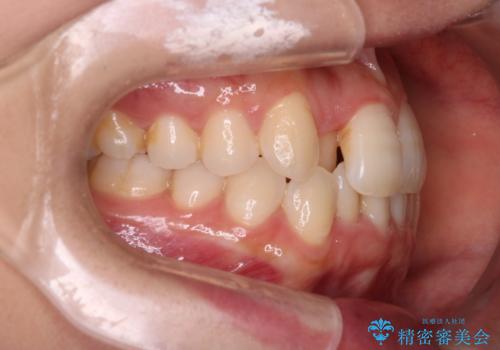

【インビザライン】前歯の凸凹をなおしたい

- 前歯の凸凹を主訴に来院されました。

上顎の急速拡大を行なったのちインビザラインにて治療を行なっております。

今回のケースは後戻りのリスクを低くし、またディスキング量を減らすために上顎の急速拡大を行なっております。